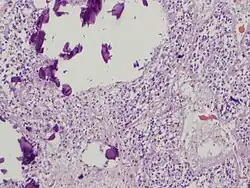

Pineal gland parenchyma with calcifications

The pineal body in humans consists of a lobular parenchyma of pinealocytes surrounded by connective tissue spaces. The gland's surface is covered by a pial capsule.

The pineal gland consists mainly of pinealocytes, but four other cell types have been identified. As it is quite cellular (in relation to the cortex and white matter), it may be mistaken for a neoplasm.[18]

Calcification

Calcification of the pineal gland is typical in young adults, and has been observed in children as young as two years of age.[33] The internal secretions of the pineal gland are known to inhibit the development of the reproductive glands because when it is severely damaged in children, development of the sexual organs and the skeleton are accelerated.[34] Pineal gland calcification is detrimental to its ability to synthesize melatonin[35][36] and scientific literature presents inconclusive findings on whether it causes sleep problems.[37][38]

The calcified gland is often seen in skull X-rays.[33] Calcification rates vary widely by country and correlate with an increase in age, with calcification occurring in an estimated 40% of Americans by age seventeen.[33] Calcification of the pineal gland is associated with corpora arenacea, also known as "brain sand".